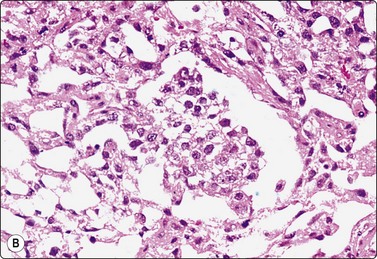

Yolk sac tumor (Figs 13.37 and 13.38)14,53-56,59-61,63

Most cytologic reports are based on FNA performed on metastatic sites. A detailed account of the morphologic spectrum of endodermal sinus tumor has been reported by Akhtar et al.53

image image

Fig. 13.37 Endodermal sinus tumor

(A) Polypoid epithelial fragment of large malignant cells with pale, almost clear, vacuolated cytoplasm (MGG, HP); (B) Corresponding tissue section (H&E, IP).

Fig. 13.38 Endodermal sinus tumor

(A) A glomeruloid cell cluster with vacuolated cytoplasm on a mucoid background (DQ, IP); (B) Cell cluster with a vascular stalk and several hyaline globules.

Criteria for diagnosis

Mucoid background,

Glomeruloid structures,

Schiller-Duval bodies (characteristic finding when present),

Very immature cells, prominent nucleolus, basophilic cytoplasm,

Small naked nuclei,

Intra- or extracellular PAS-positive hyaline globules (AFP positive),

Prominent cytoplasmic vacuoles and distinct cell boundaries confer a clear-cell appearance,

Immunocytochemistry: focal staining for AFP, AE1/AE3 and PLAP; negative for OCT image.

Pure yolk sac tumors are almost always encountered in infants and young children but rare in the first 6 months of life.49 In adults, this pattern is seen in approximately 40% of nonseminomatous GCT;12 however, it can easily be mistaken for embryonal carcinoma in FNA smears. This is why most reported cases are of metastatic tumors. Hyaline globules and eosinophilic membrane-like material are hints to the diagnosis of this tumor type (Fig. 13.38B). In infants and young children, the aforementioned cytological criteria permit a confident diagnosis by FNA.